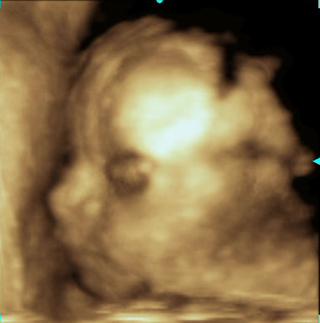

Caute kocky tak sme boli vcera na velkom utz a je to chlapcek, mame 460g a 25cm ,dr povedal ze take ukazkove organy ako do ucebnice uz davno nevidel 😵 😵 😵 a asi v polovici vysetrenia si maly zavcal davat ruky medzi nozicky a chytal si pipika dr. bol uplne vyvaleny 😀 😕 a tak sme sa smiali 😀 ze este je v brusku a uz si ho zmoli 😵 proste typicky chlap 😀 😀 😀 😀

sme proste s tatinom stastni ze je malinky v poriadku 😵 😵 😵 😵